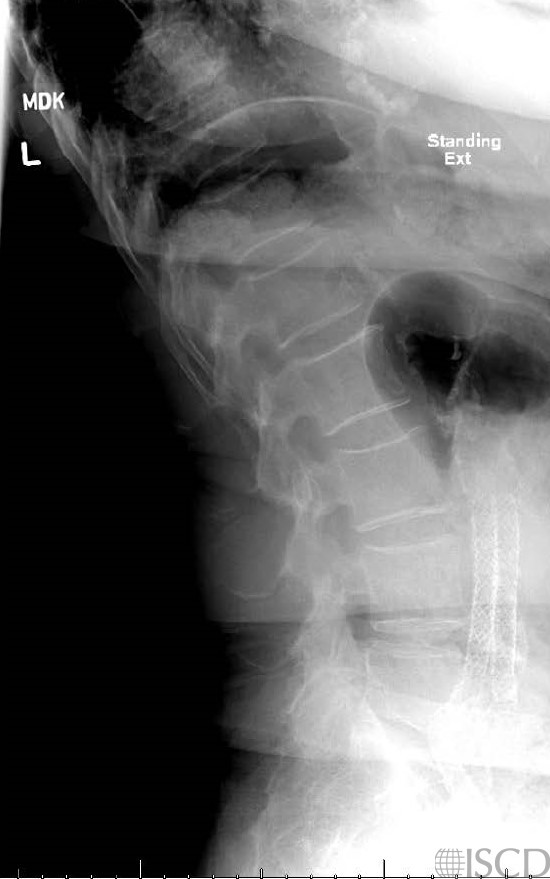

This is the accompanying lateral radiograph showing the iliac stents.

The Hologic lumbar spine DXA shows common iliac stents overlying L4. Therefore, L4 is omitted from analysis. The accompanying lateral radiograph also demonstrates the iliac stents.